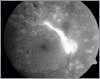

Netzhautbilder: gesund und bei Diabetes

Diabetes und Auge

Dank der Möglichkeiten der Lasertherapie kann bei rechtzeitigem Beginn das Schicksal, durch diabetische Retinopathie zu erblinden, vermieden werden.

Wenn eine Laserbehandlung erforderlich ist, kann diese nach Fluoreszenzangiographie gezielt eingesetzt werden. Die Behandlung ist gut verträglich und nicht schmerzhaft.

Folgen eines zu späten Behandlungsbeginns dieser Erkrankung können zu Sehschärfenverlust bis zur Erblindung, Katarakt (grauer Star) und Glaukom (grüner Star) sowie Glaskörpereinblutung und Netzhautablösung führen.

Einblutungen des Glaskörpers durch defekte Gefäße können Vitrektomien (Glaskörperentfernungen) und Silikonölfüllungen des Auges erfordern.